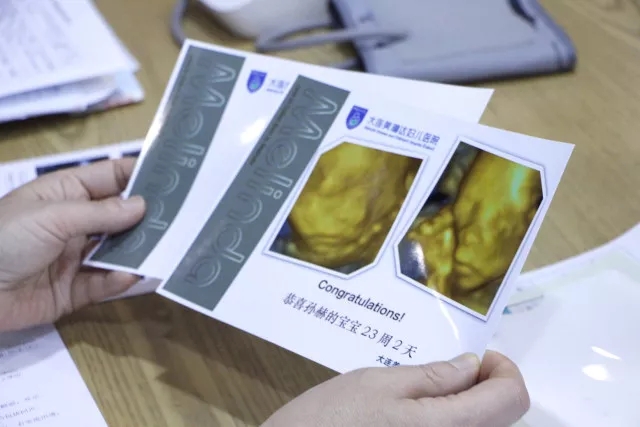

大连四维彩超医院:美琳达科普孕期做四维彩超的作用,四维彩超可以清楚看到胎儿在子宫内的情况,可以从不同的角度观察到宝宝的生长发育状况,能尽早了解到胎儿患有的一些先天性疾病,同时还能检查到孕妇有无妇科疾病等等。孕妇一定要重视四维彩超这项检查,对于胎儿与孕妇有健康有诸多帮助。

胎儿在妈妈子宫内的情况通过四维彩超能清晰看到,还通过不同的角度,可以观察到宝宝的生长发育情况,对于宝宝存在的先天性疾病和先天性畸形都是可以看出来的。对于母体来说,也可以看到母体是否有子宫肌瘤、卵巢囊肿、还可以对这些疾病进行跟踪了解。

1、面部畸形:四维彩超检查重点要看胎儿的双眼以及眼眶是否一样大、等圆,以及眼距测量,硬腭、软腭及上唇弧型曲线是否连续中断等。然后再查看一下胎儿的颈部,主要看一下有没有异常包块。

2、脊柱畸形的筛查主要是查看脊柱是否有隆起,光带有没有中断,排列是不是紊乱,骶尾部有没有肿块等。还有腹部畸形、肢体畸形通过检查也比较容易发觉。

3、四维彩超主要检查神经系统:无脑儿、脑积水、小头畸形、脊柱裂及脑脊膜膨出。在四维彩超胎儿筛畸检查中,首先要筛查的是头颅畸形。

4、检查中,检查者会严谨地观察胎头形态、脑组织(丘脑、小脑、小脑蚓部、颅后窝池、侧脑室)以及中线距两侧颅骨板的距离等,筛查无脑儿、露脑、脑积水等情况。

5、检查尿系统、肾积水、多囊肾及巨膀胱、尿道梗阻。

6、最主要的是四维彩超主要检查消化系统:脐部肠膨出、内脏翻出、肠道闭锁及巨结肠等。短肢畸形、联体畸形、先天性心脏病及畸胎病等。